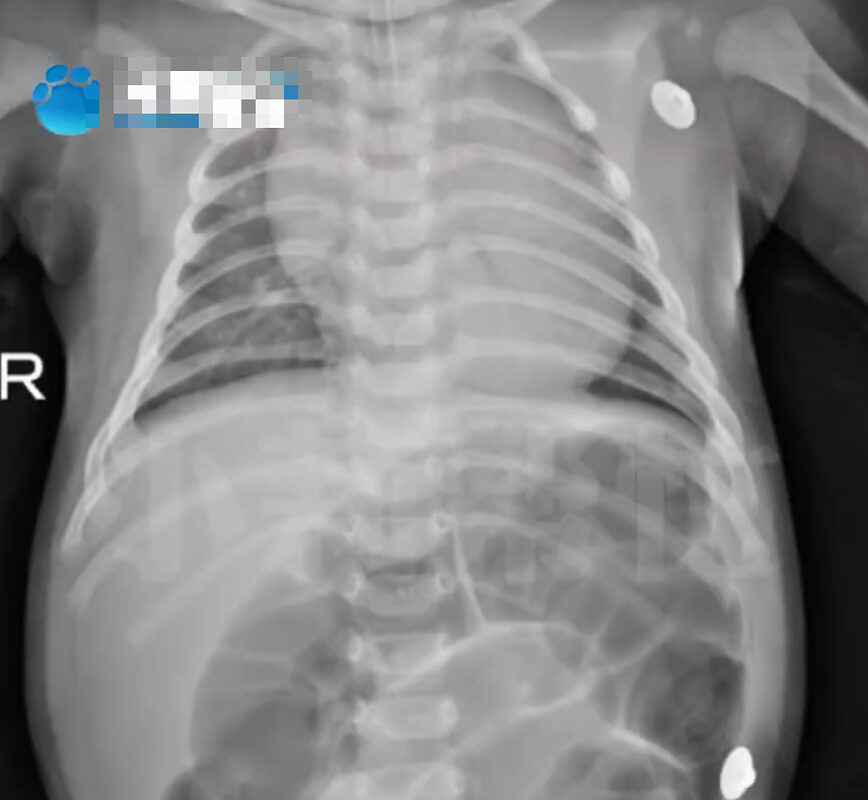

Một vụ việc thương tâm xảy ra tại Hà Nam (Trung Quốc) khiến nhiều người, nhất là các gia đình có con nhỏ phải giật mình. Cụ thể, một bé gái chỉ mới 52 ngày tuổi nhập viện cấp cứu tại Bệnh viện nhi đồng Hà Nam trong tình trạng bụng phình to, khó thở nghiêm trọng. Kết quả chẩn đoán là ngộ độc Botulinum nguy kịch.

Em bé 52 ngày tuổi nhập viện trong tình trạng bụng phình to, suy hô hấp vì ngộ độc Botulinum